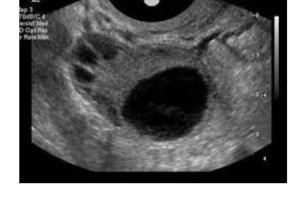

窦卵泡计数(AFC)

窦卵泡计数(AFC简介) AFC是窦卵泡计数的缩写,是指利用B超彩超等等对卵巢的卵泡数目、大小来进行其的计数手段之一,而窦卵泡常说的是女性卵巢内直径在2-10mm的小卵泡,而通过窦卵泡计数也能够非常好的反应出卵巢储存功能等等。 英文名:AFC 专属:女性 类型:微型卵细胞 生成:卵巢 针对人群:高龄…